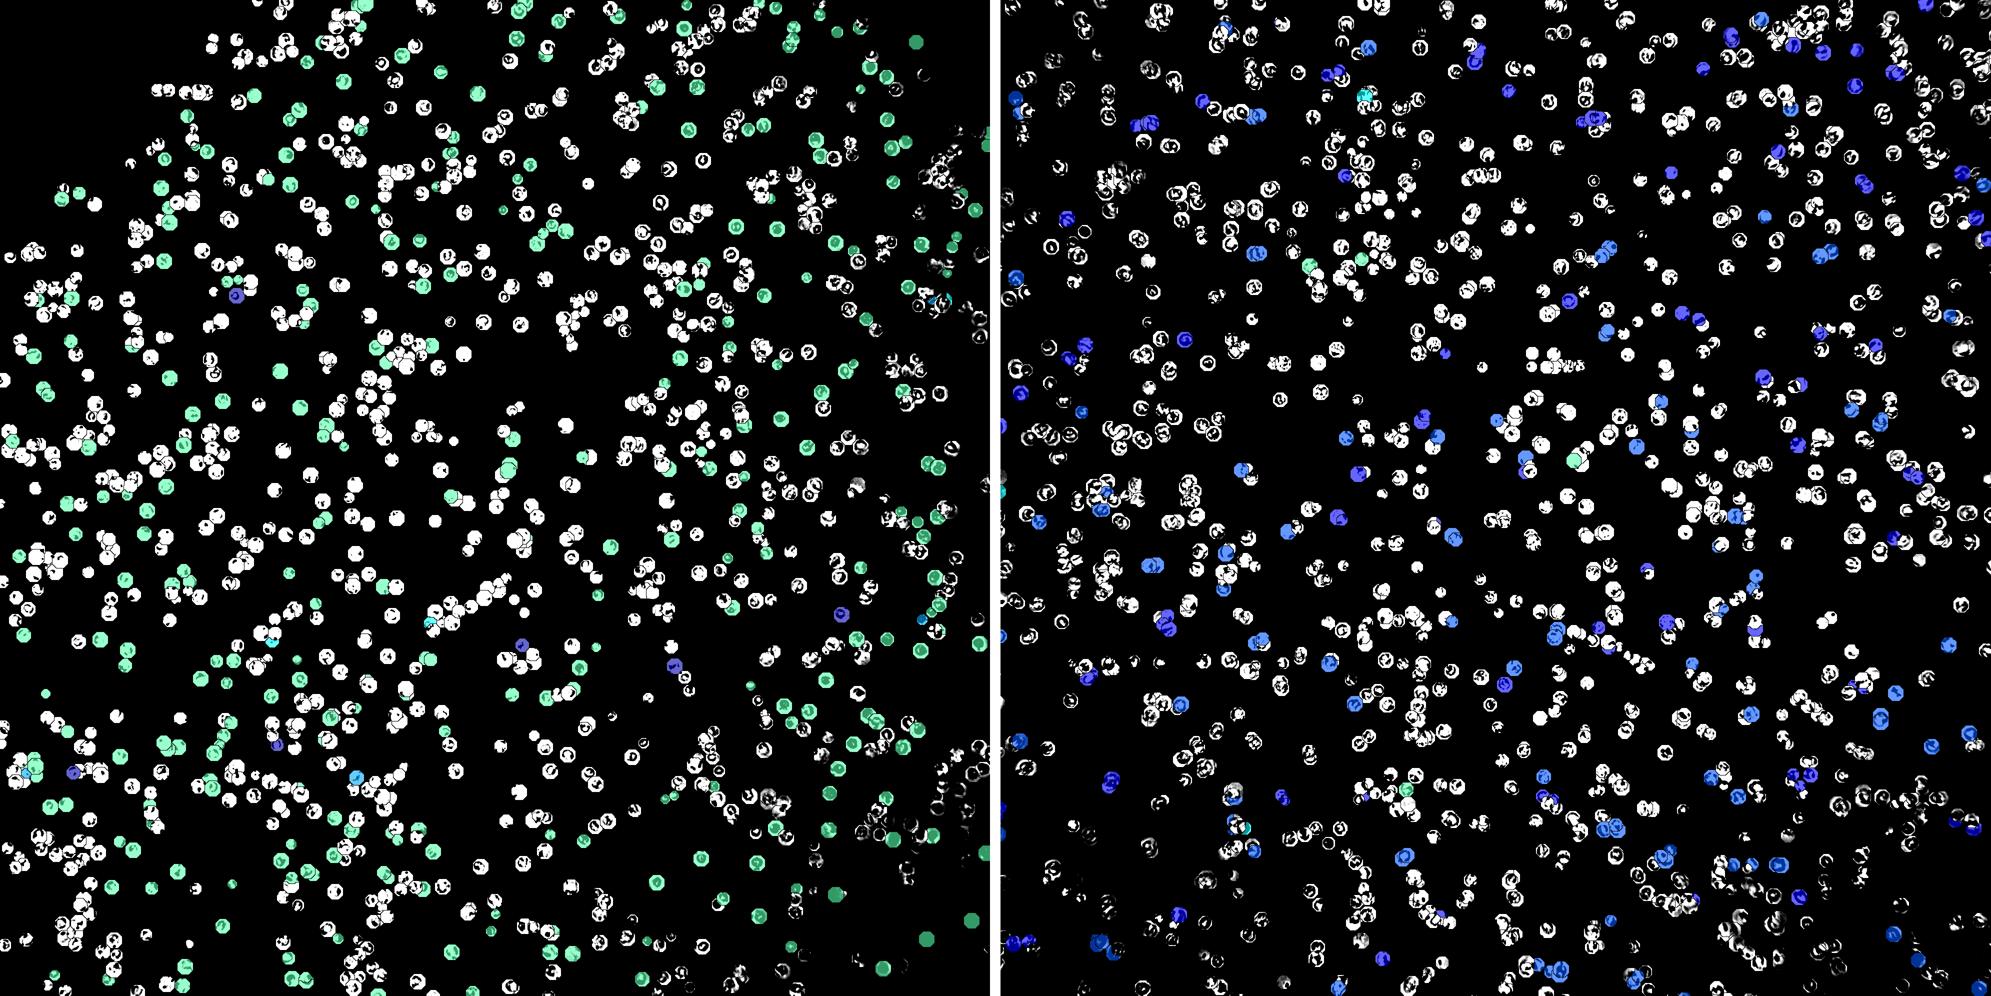

Cells labelled with CD15 CD8a

Peripheral blood lymphocytes

Inflammatory Disease

Cell populations before and after treatment